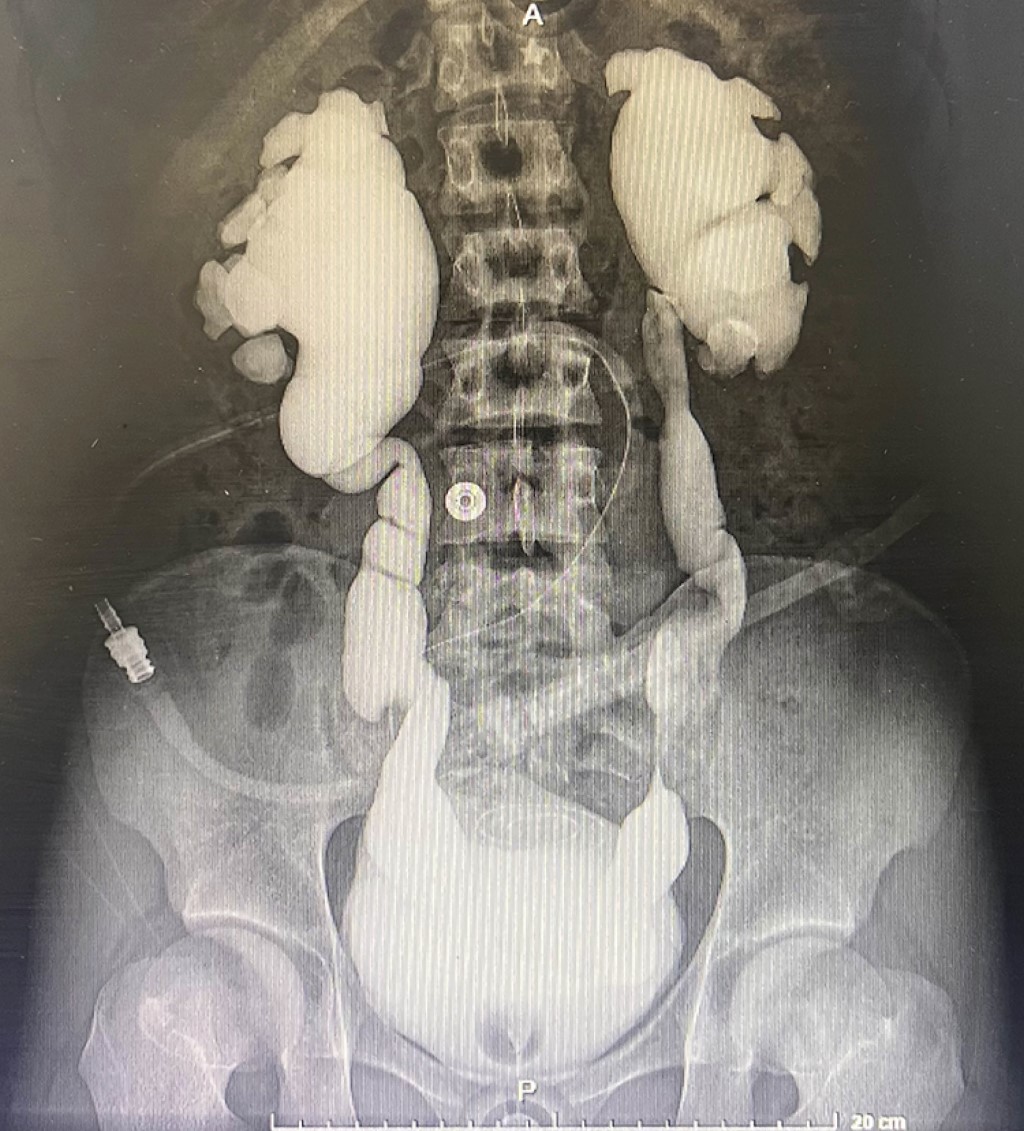

Laparoscopic bilateral pre-transplant nephrectomy in a patient with grade IV vesicoureteral reflux and chronic kidney disease

A bilateral transperitoneal laparoscopic nephroureterectomy was performed on pre-transplant natives through five ports with a change in modality from peritoneal dialysis to renal replacement, removing the Tenckhoff catheter through a mid-infraumbilical wound for the extraction of both native kidneys and placement of a Mahurkar catheter. Surgical time: 180 min, intraoperative blood loss 100 mL, hospital stay: 48 h. After 30 days, living donor kidney transplant performed, warm ischemia 4 min, cold ischemia time (CIT) 91 min, uremia. Discharged on the fifth postoperative day. Serum creatinine (Cr) 1 mg/dL, hemoglobin 6.7 mg/dL without transfusion requirement, maintained transurethral catheter at home for four days until urinary volumes decreased and intermittent bladder catheterization program was restarted. Follow-up four months post-transplant: Cr 1.14 mg/dL, hemoglobin 14.1 mg/dL.

Figure 1